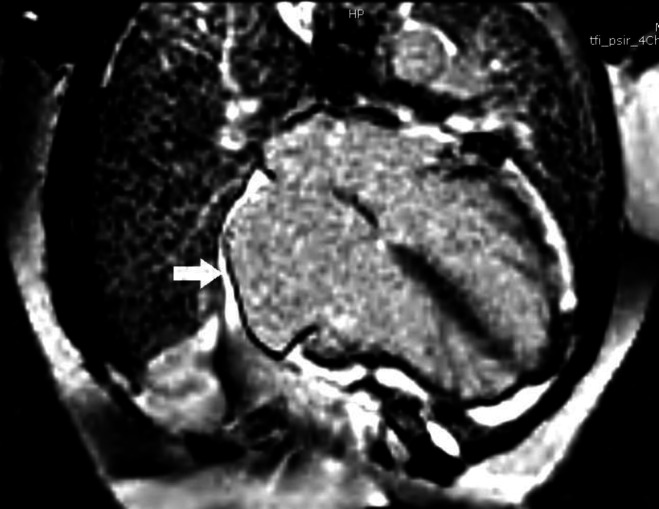

慢性缩窄性心包炎由于长期压迫心肌,会出现心力衰竭的症状和体征。当心包增厚和纤维化时,手术是唯一的治疗策略。手术可改善患者的功能状态,提高存活率,但同时也会带来严重的死亡率和发病率。多年来,治疗这种病症的手术方法基本保持不变,但缩窄性心包炎的病因机制已从主要是结核病转变为心脏手术后病变和特发性病变。本综述概述了缩窄性心包炎的外科治疗。

Chronic constrictive pericarditis results in the signs and symptoms of heart failure due to the chronic compression of the myocardium. When the pericardium becomes thickened and fibrosed, surgery is the sole curative management strategy. Surgery leads to an improvement in functional status and survival, but it is associated with significant mortality and morbidity. Over the years, the surgical approach to this pathology has largely remained unchanged, but there has been a shift in the etiological mechanism of constrictive pericarditis from predominantly tuberculous to post-cardiac surgery and idiopathic pathologies. This review offers an overview of the surgical management of constrictive pericarditis.